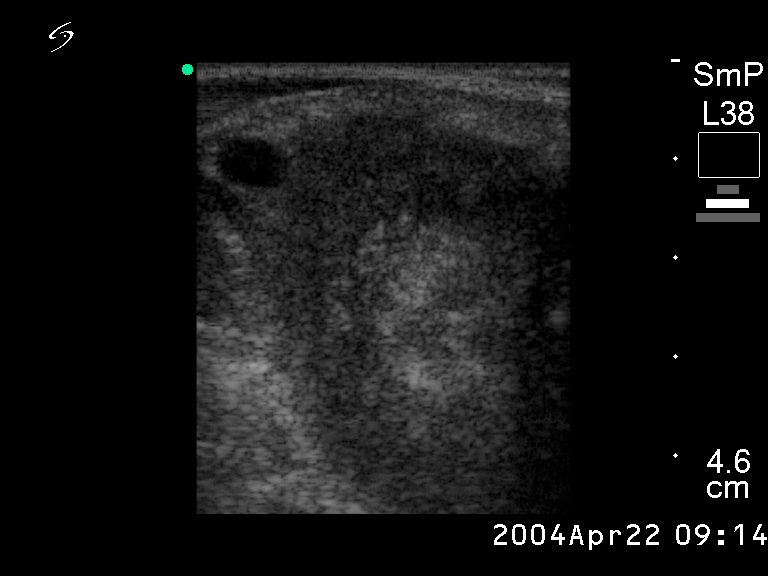

Ultrasonography. A large, hypoechogenic mass occupied almost the entire right lobe. The tumor spread substernal.